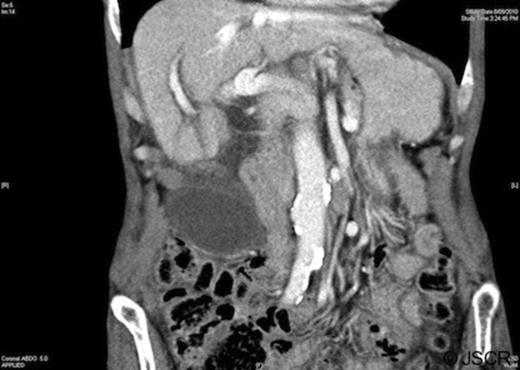

Blood tests were unremarkable, demonstrating a mild anaemia and normal liver function. White cell count (7.8×109/L) and C-reactive protein (<5mg/L) were within the normal range. Abdominal ultrasound and computed tomography revealed a large distended, low-lying gallbladder with a diffusely thickened wall (up to 6mm), pericholecystic fluid and no cholelithiasis (Figure 1). The biliary tree was normal in calibre and ultrasound Murphy’s sign was positive.

Computed tomography demonstrating a low-lying gallbladder with a diffusely thickened wall and pericholecystic fluid

Pre-operative diagnosis of gallbladder torsion remains uncommon, owing to the rarity of the condition and the non-specific clinical and radiological features. Ultrasound will often demonstrate a thickened gallbladder wall with pericholecystic fluid. The gallbladder may appear to lie below its normal anatomic fossa, and may have an echogenic conical structure (representing the twisted pedicle) at the gallbladder neck (7). Stones may be an incidental finding (reported in 24.4% of cases in one study (8)), but are not thought to play any role in the aetiology of the condition. Similarly, computed tomographic scans may reveal an abnormal anatomical position for the gallbladder, as well as wall thickening and pericholecystic fluid.